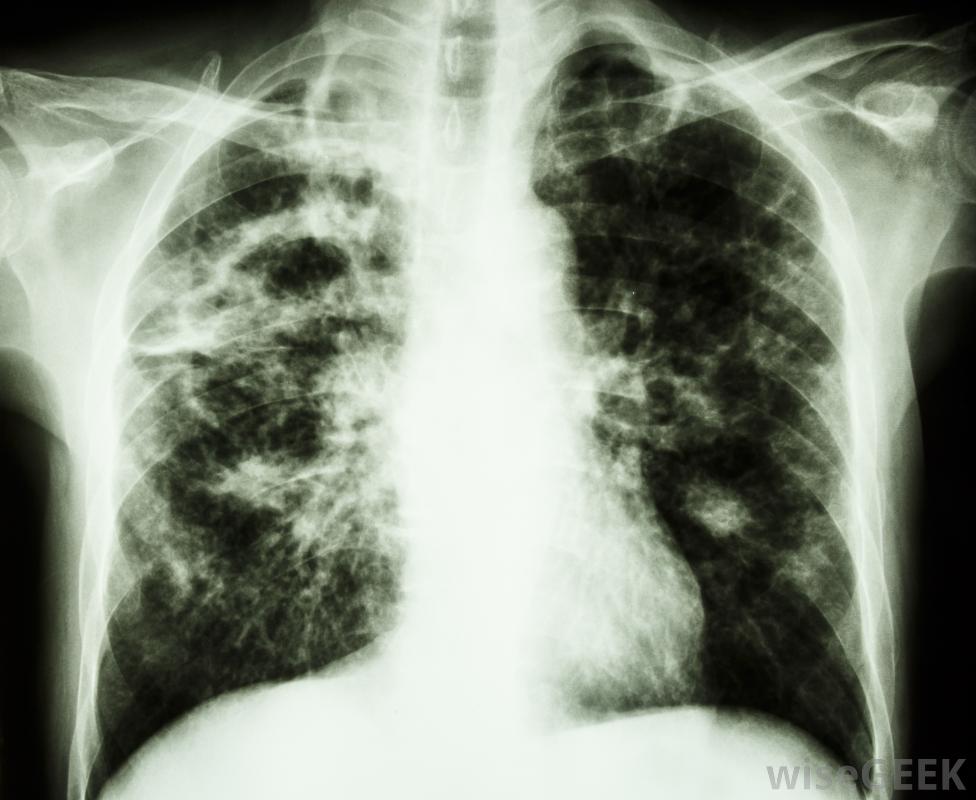

通常,肺结核会感染肺部,但在免疫系统较弱的患者中,它可能发生在淋巴结等部位。通常,肺结核感染肺部,但在免疫系统减弱的病人中,它有时会发生在肺外,比如淋巴结。国王的邪恶和淋巴结这个词专门指的是影响颈部淋巴结的结核病,而不是身体其他部位的淋巴结。在几乎所有的病例中,这种疾病成人是由结核分枝杆菌引起的。在所有的传染病中,结核病是有记录以来最古老的一种类型,人们认为自古以来就有国王的邪恶影响着人们

结核病通常在肺部生存和繁衍,尽管它可能传播到其他区域,如淋巴结英国的忏悔者爱德华和法国的菲利浦一世是第一批触摸贪腐病人的国王,据说是为了治愈国王的罪恶。参加仪式接受王室抚摸的人会得到金币,人们普遍认为它具有神奇的力量。一旦国王的邪恶病人开始使用皇室触摸术,后来的国王就被认为继承了这种特殊能力。

肺结核的症状可能包括疲劳和咳嗽。一些君主触碰了许多受国王邪恶折磨的人。据认为,路易十五可能接触了超过2个,1825年,查理十世是法国国王中最后一个实行这种做法的国王。英国国王中最后一个对他们贪婪的臣民施以皇室色彩的人实际上是一位女王,安妮女王,她的统治一直持续到1714年X光片可以用来诊断肺结核,人们认为治愈国王邪恶所需的力量已经转移到被国王触摸过的硬币上。这种情况发生在14世纪,硬币被称为天使。即使天使停止生产,人们也相信触摸一枚外观相似的金质奖章也会有同样的神奇效果更现代的治疗方法通常包括服用几种不同的抗生素长达一年